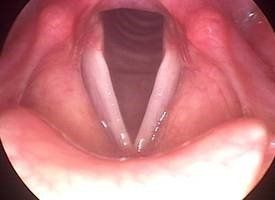

A Terni lo studio del Dr. Santino Rizzo dispone di apparecchiature e attrezzature diagnostiche che consentono di eseguire approfonditi esami audiologici analizzando anche le parti più interne dell'orecchio. Per la chirurgia dell'orecchio e per le visite specialistiche dell'udito si avvale di dilatatori della tromba di Eustachio, strumenti che lavorano per via endoscopica, strumenti per la chirurgia estetica e funzionale del naso e di aerazione, strumenti di rinofibrolaringoscopia flessibile, microlaringoscopia, laringoscopia indiretta e audiometria.